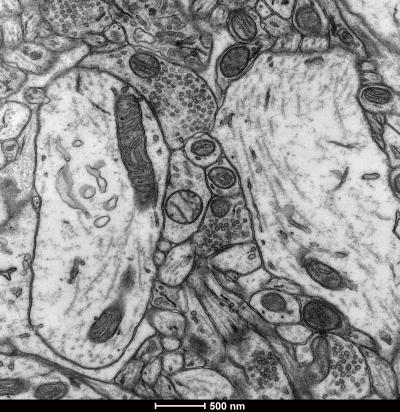

The nucleus accumbens of these particular rats showed a reduced energy metabolism. This involves the mitochondria, which are the cell's organelles that are in charge of breathing and energy production. The researchers found that the high-anxious rats showed lower mitochondrial function than more relaxed ones.